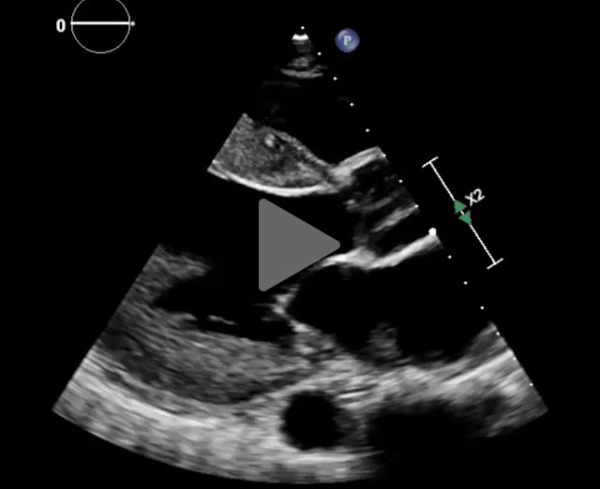

L'ETT montre :

- Dilatation modérée du VG. FEVG à 30%

- Cardiopathie hypertrophique sévère excentrique

- Flux mitral restrictif

- Ventricule droit non dilaté

- Paroi libre épaissie

- Minime épanchement péricardique circonférentiel

Vidéo 1